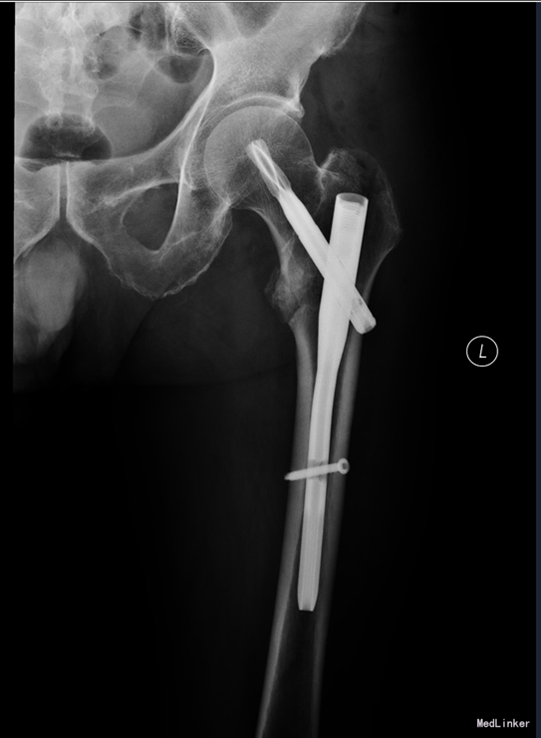

患者2014-04-27日上午9时摔倒后左髋部疼痛肿胀、活动受限,不能站立行走,急来中国医科大学附属盛京医院急诊科,急诊予以行辅助检查,左下肢DR提示:左股骨粗隆间骨折,现患者为求进一步诊治,以“左股骨粗隆间骨折”为诊断收入我科。患者自受伤以来一般状态可,无发热,无头晕、呕吐,无胸闷、心悸呼吸困难,无腹痛、腹泻,饮食可,睡眠可,二便正常。

左髋部未见明显肿胀及瘀斑,活动度减低,活动因疼痛受限,左髋部压痛阳性,叩击痛阳性,左下肢缩短畸形,缩短1cm,外旋80°。左膝及左踝关节活动无明显异常。双侧足背动脉搏动有力,肢体末梢血运良好,皮温正常。远端足趾感觉运动正常,

入院后完善检查,查无手术禁忌症后行左股骨粗隆间骨折闭合复位内固定术。患者术后第二天下地行走,术后3天自动退院。